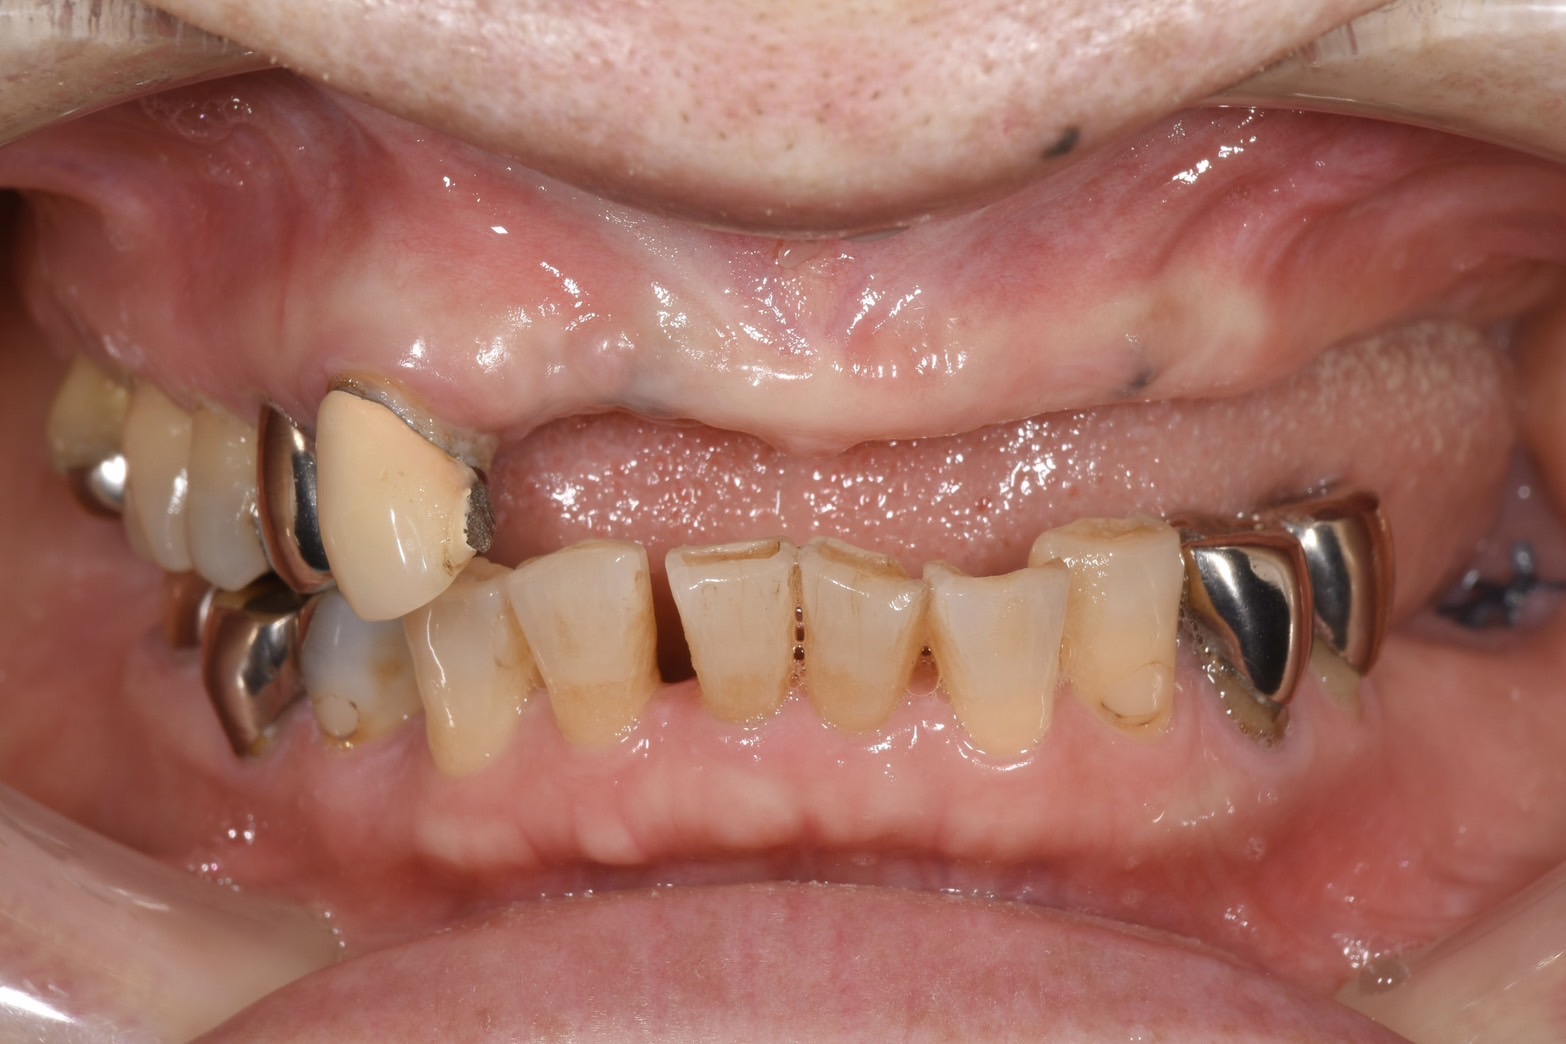

• 前歯のインプラント抜歯即時埋入

前歯のインプラント抜歯即時埋入

• インプラント抜歯即時埋入

インプラント抜歯即時埋入